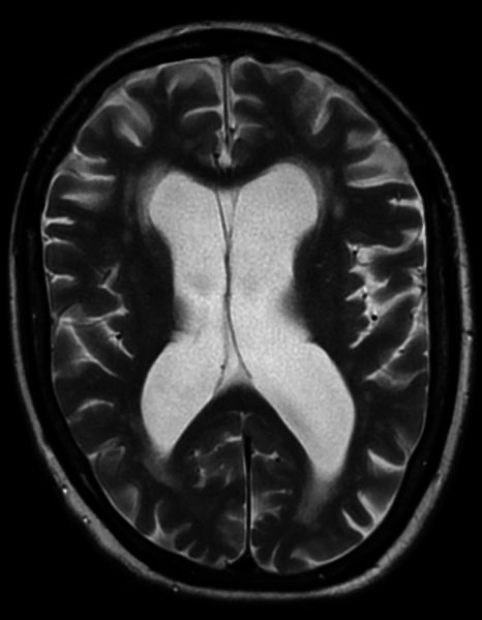

Vascular Dementia: What is the hallmark of diagnosis via MRI?

White matter and infarcts